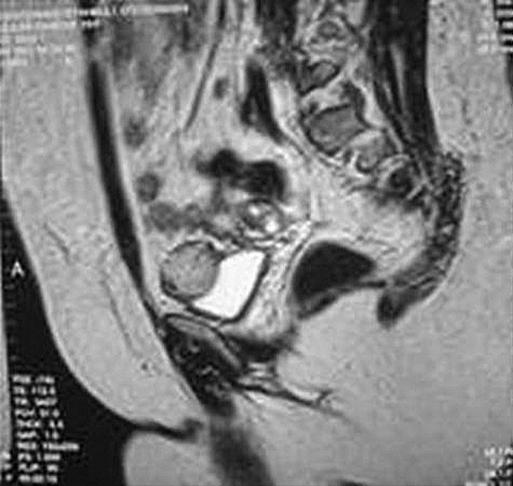

Bladder pheochromocytomas are extremely rare and constitute less than 5% of bladder tumors. The initial symptoms of the patient are mostly nonspecific caused by hypertension. The postmicturition hypertensive crisis is the typical warning sign of this disease. In this article, we present a 29-year-old female having hypertensive attacks following micturition. Radiological imaging techniques revealed a 3 x 3 x 4-cm bladder tumor that was hormonally active. This is the first case reported of bladder pheochromocytoma that was laparoscopically treated without using the adjunct transurethral resection. The postoperative follow-up of the patient confirms the success of the surgical procedure.

膀胱嗜铬细胞瘤极为罕见,占膀胱肿瘤的比例不到5%。患者的初始症状大多由高血压引起,缺乏特异性。排尿后高血压危象是该病的典型警示信号。在本文中,我们介绍了一名29岁的女性,她在排尿后出现高血压发作。放射影像学检查发现一个3×3×4厘米大小、具有激素活性的膀胱肿瘤。这是首例报道的经腹腔镜治疗且未辅助经尿道切除术的膀胱嗜铬细胞瘤病例。对该患者的术后随访证实了手术的成功。